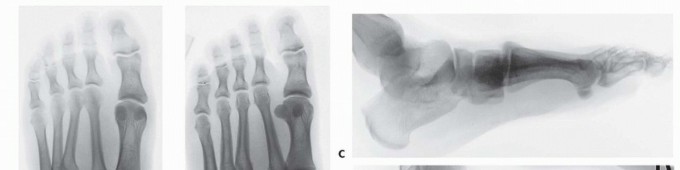

Initial radiographic evaluation consists of non-weight-bearing anteroposterior (AP), oblique, and lateral views of the foot, which, depending on the extent of intra-articular displacement, may provide sufficient diagnostic information (

FIG 3A-C

).

Fluoroscopic stress views may be helpful in more subtle injuries; however, these studies are painful and generally require anesthesia.

We therefore prefer weight-bearing radiographs of the foot for more subtle injuries (

FIG 3D-H

); comparison weight-bearing radiographs of the contralateral foot may also be obtained where necessary.

The weight-bearing AP view of the foot will demonstrate intra-articular displacement through the first and second tarsometatarsal joints (so-called Lisfranc joint), intercuneiform joint, and naviculocuneiform joint; fractures through the first and second metatarsal bases, medial and middle cuneiforms, and proximal extension into the navicular; and the extent of columnar shortening or asymmetry.

The medial border of the second metatarsal should align with the medial border of the middle cuneiform (

FIG 3D

The oblique view will reveal intra-articular displacement through the third, fourth, and fifth tarsometatarsal joints and fractures of the third, fourth, and fifth metatarsal bases, lateral cuneiform, and cuboid.

The medial borders of the third and fourth metatarsals should align with the medial borders of the lateral cuneiform and cuboid, respectively (

FIG 3E

The lateral view may reveal dorsal-plantar displacement of fractures or dislocations as well as any flattening of the medial longitudinal arch, thereby reflecting the status of the weight-bearing medial column and first ray (

FIG 3F

FIG 3

• Non-weight-bearing AP (

A

), oblique (

B

), and lateral (

C

) radiographs of grossly unstable, purely ligamentous, Lisfranc dislocation involving all five tarsometatarsal articulations. Marked lateral subluxation through all five tarsometatarsal joints is evident on the AP and oblique views, and significant dorsal displacement is evident on the lateral view. Weight-bearing lateral (

D

), AP (

E

), and oblique (

F

), and non-weight-bearing (

G

) and oblique (

H

) radiographs of more subtle Lisfranc injury. Lateral and plantar subluxation (

black arrows

) is evident on the weight-bearing radiographs, and displacement of normal radiographic landmarks (

black lines

) confirms injury.